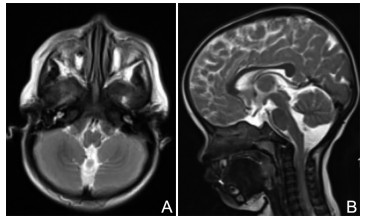

EBF3变异所致肌张力减退-共济失调和发育迟缓综合征患儿1例及文献复习

李慧晶, 阮妙华, 王丹, 卢朝升

2026, 24(1): 168-170. doi: 10.16766/j.cnki.issn.1674-4152.004354

82 5

摘要:

分析2024年8月就诊于温州医科大学附属第一医院儿童神经内科的1例肌张力减退-共济失调-发育迟缓综合征(hypotonia-ataxia-developmental delay syndrome,HADDS)患儿的临床表型及遗传学病因,患儿为1岁2个月,因“发育迟缓半年余”就诊。临床表现为肌张力减退、全面发育迟缓、异常面部特征及共济失调等。家系全外显子组测序发现患儿EBF3基因存在c.1038C>A(p.Y346*)无义变异,Sanger测序验证父母均无此变异。经分析,依据美国医学遗传学与基因组学学会标准,该变异被判定为致病性。通过复习文献总结相关疾病临床表现与遗传学特征,该病例不仅扩展了EBF3变异所致HADDS的变异谱,还丰富了其临床表型,为该疾病研究提供了新的案例与依据。